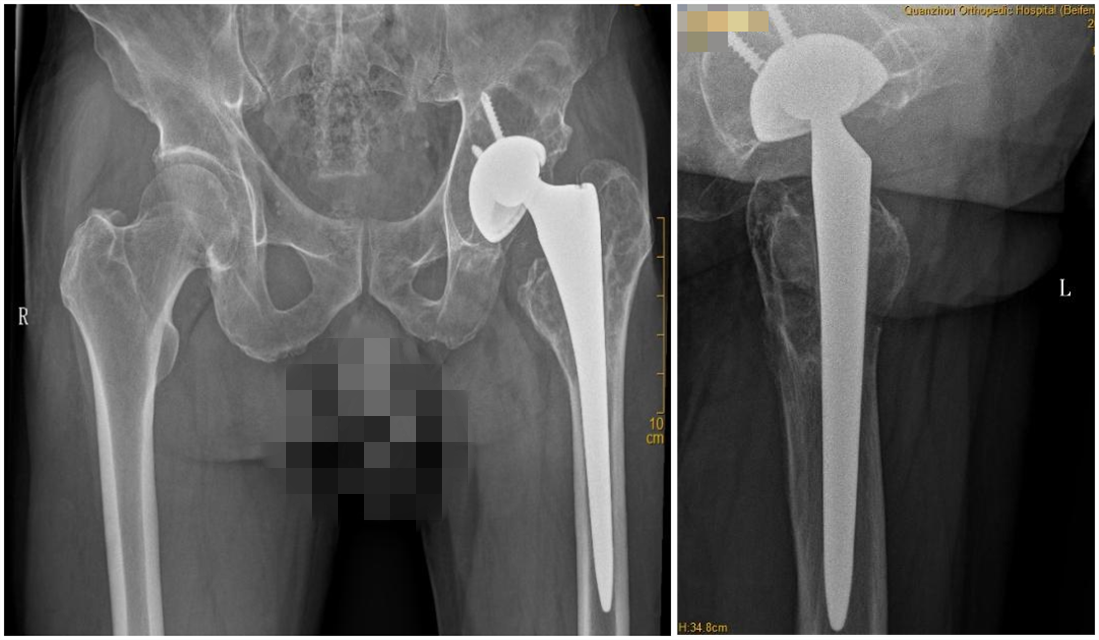

[关节科] 【正骨科普】换了髋关节十几年,如今却行走困难……专家提醒:这个“保养” 日期:2026-01-06 17:04:00 点击: 好评:0